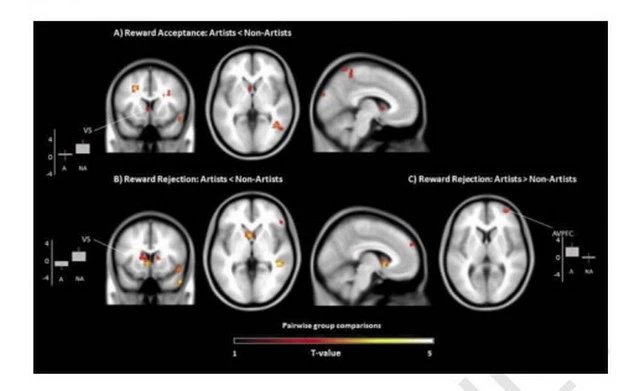

Пока испытуемые проходили тест, исследователи сканировали активность их мозга с помощью функциональной магнитно-резонансной томографии (фМРТ). Обнаружилось, что творческие люди показали значительно меньшую активацию в вентральном стриатуме, части «системы вознаграждения» мозга, когда выбирали «денежные» зелёные квадраты по сравнению с нехудожниками.

Сканирование мозга в ходе изучения дофаминергической системы вознаграждения художников и нехудожников в новом исследовании «Реактивность системы вознаграждения у художников при принятии и отказе от денежных вознаграждений» в журнале Creativity Research Journal.

Во втором тесте исследователи обнаружили, что люди творческих профессий показали большую активацию в другой части мозга, связанной с допамином (префронтальная кора), когда им сказали отказаться от зелёных квадратов. Другими словами, мозг творческих людей положительно реагирует на процесс, а не на материальный результат и они лучше работают, когда знают, что им не заплатят.